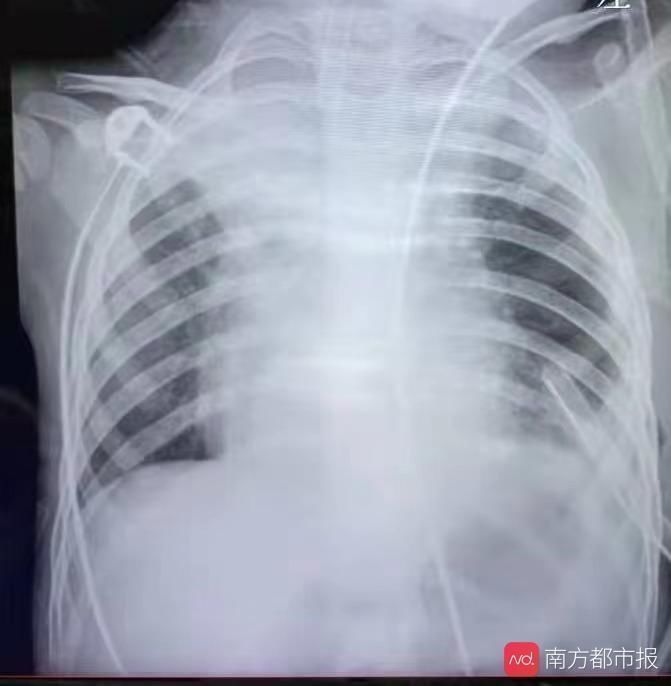

手术后,原本被挤占的肺、心开始回归正常位置